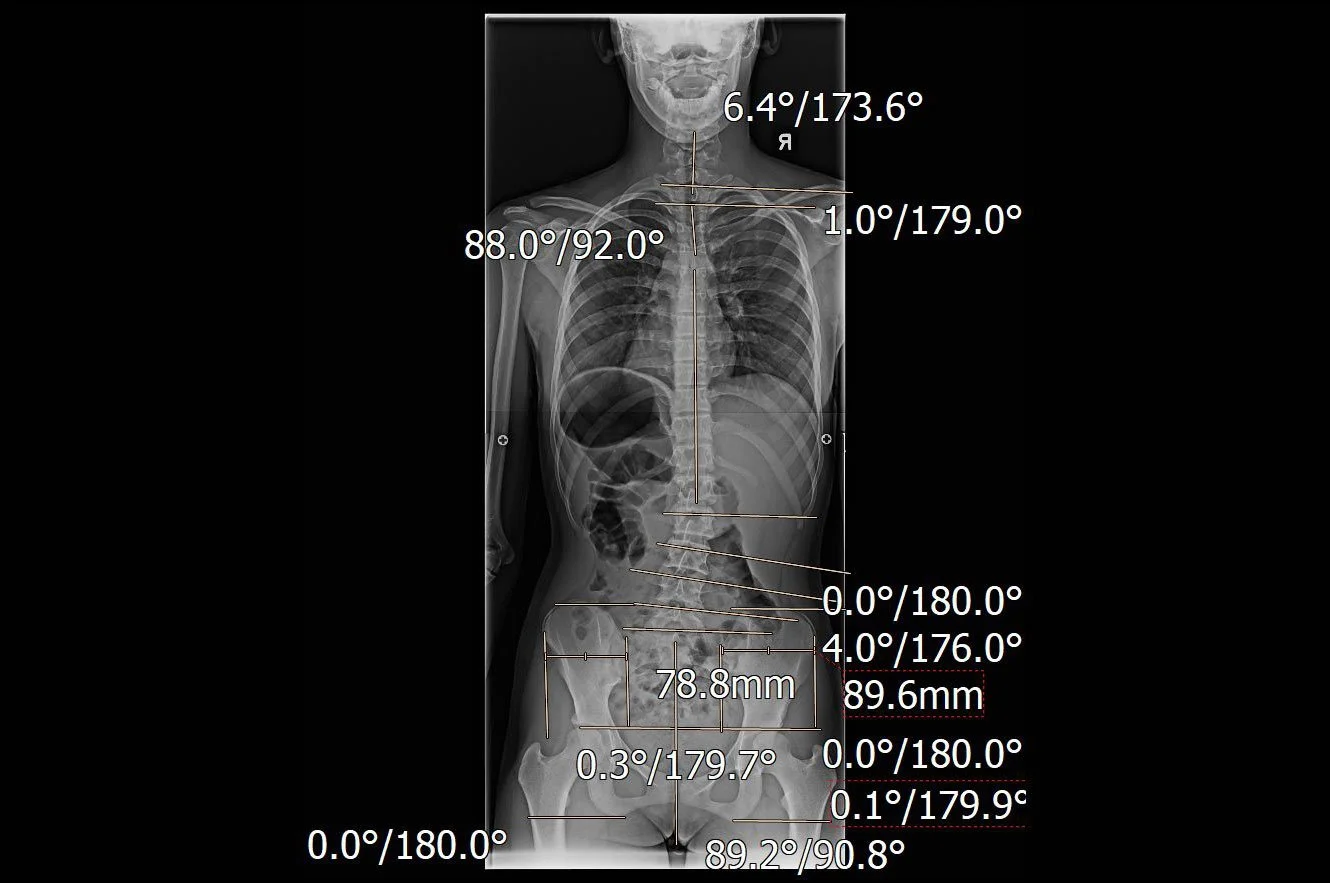

Der Untersuch beginnt mit der Beobachtung der Haltung im Stand in zwei Ebenen sowie zusätzliche Untersuchungen wie z.B. die Studie mit dem Global Posture System (GPS) oder eine Gang-Analyse.

Das Röntgenbild gibt weitere wichtige statische Hinweise; es hilft mir auch, die Richtung zu bestimmen, in die ich ein Segment korrigieren möchte.